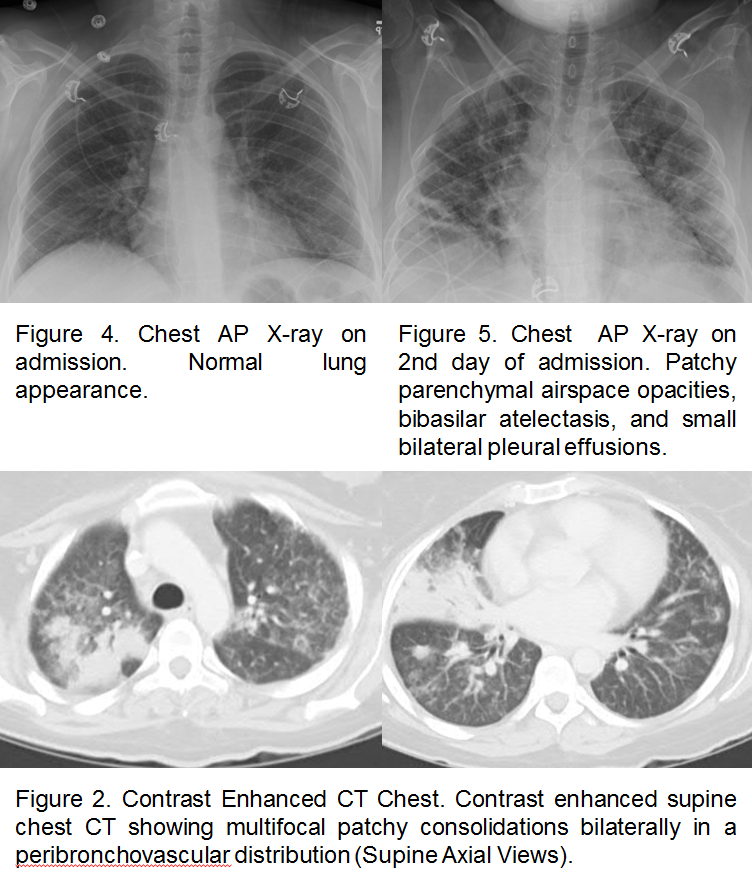

Case Presentation: A 32-year-old woman with history of lupus not on steroid or immunosuppressive therapy for more than 10 years presented with headache, generalized weakness, abdominal pain, nausea, vomiting, and malaise. On exam, the patient was afebrile with tachycardia and hypotension. She was ill-appearing with a diffusely tender abdomen, mild hepatomegaly, and enlarged axillary and inguinal lymph nodes. Neurologic and pulmonary examination was normal. Laboratory evaluation was significant for a white blood cell count of 49 x 10^9/L with 55.4% atypical lymphocytes, elevated liver enzymes and positive ds-DNA antibodies. Plain film of the chest was unremarkable, and computed tomography of the abdomen showed hepatosplenomegaly and diffuse lymphadenopathy. The patient was admitted with the diagnosis of sepsis and treated with fluids and antibiotics. On the day of admission, the patient developed confusion and blurring of vision. An extensive work up including brain magnetic resonance imaging, ophthalmologic examination, and lumbar puncture were negative. Lymph node biopsy and flow cytometry were negative for hematologic malignancy. Cytomegalovirus IgG and IgM serology was positive with a viral load of 9,140 by cytomegalovirus DNA polymerase chain reaction. The patient remained afebrile during admission developed hypoxic respiratory failure and required intubation. Chest imaging showed multifocal patchy infiltration bilaterally. Bronchoscopy sampling was positive for cytomegalovirus. She was treated with ganciclovir with significant improvement and complete recovery on follow up visit.